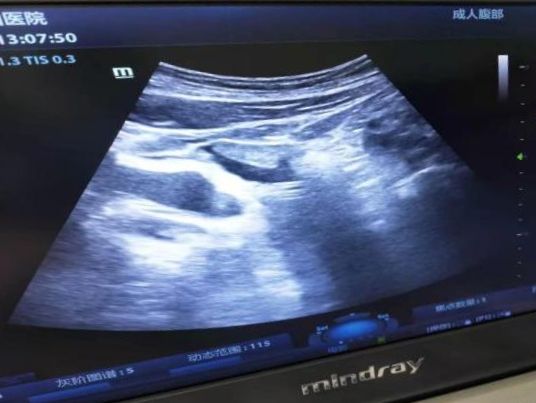

手术在门诊手术室进行,在上级医院专家指导下,东院肾脏内科孙芳副主任医师及贺海燕主治医师在超声引导下采用Seldinger法分别为两位患者成功实施了手术。患者术后恢复良好,腹膜透析治疗顺利。

超声下观察腹透管位置